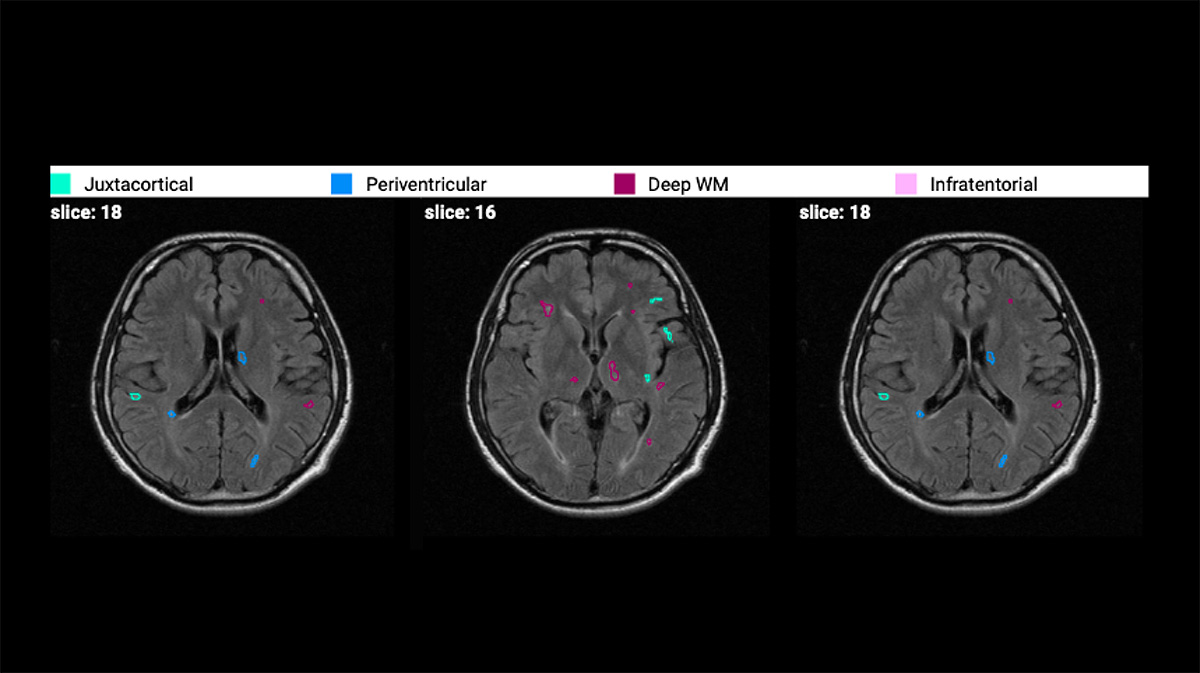

Distinct color-coding for periventricular, deep white matter, juxtacortical, and infratentorial regions overlays on FLAIR images, enabling immediate visual assessment of lesion distribution patterns critical for differential diagnosis support.